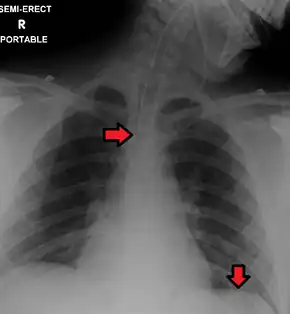

Confirming placement

It is necessary to confirm placement of the endotracheal tube to ensure that the tube is properly positioned within the trachea and has not accidentally passed into the esophagus instead. Additionally, it is important to confirm that the endotracheal tube was not placed too deep in the trachea where is may only be ventilating one of the lungs due to it being positioned within a mainstem bronchi (frequently the right mainstem bronchi due to a more obtuse angle than the left). The gold standard for confirming successful placement of an endotracheal tube is direct visualization of the tube passing through the vocal cords and positive end-tidal carbon dioxide on capnography. Secondary methods of confirmation include oxygen saturation, chest x-ray, ultrasound, condensation in the endotracheal tube, equal chest rise, breath sounds heard on both sides of the chest (often with the assistance of a large tidal volume breath), and an absence of breath sounds over the epigastrium. No single method of confirming placement is 100% reliable so multiple methods of confirmation should be utilized.[6][17][18]